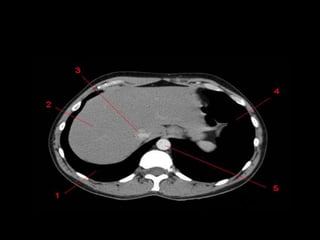

Mediastino Posterior

• Esôfago, aorta descendente, veias ázigo e

hemiázigo, ducto torácico e nervos

intercostais e autônomos.

Aorta Descendente

• Inicia em T4

pelo lado

esquerdo e

durante o

trajeto

caminha

para a

parte

posterior

ao esôfago.